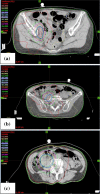

The incidence of endometrial serous carcinoma (ESC) has been increasing, and ESC is resistant to treatment. We report a patient with ESC who responded to radiotherapy for multiple recurrences. The first recurrence was detected in the vaginal wall and left internal iliac lymph node 5 months after the initial treatment. Concurrent chemoradiotherapy (CCRT) was administered. Radiation was delivered using the intensity modulated radiation therapy technique. The second recurrent tumor was detected in the right internal iliac lymph node after 4 months, and CCRT was conducted. After 4 months, the third recurrence was detected in the right common iliac node, and CCRT was performed. After 8 months, the fourth recurrence was detected in the horizontal portion of the duodenum, and radiotherapy was administered. After 9 months, the fifth recurrence was detected in the vaginal wall. Interstitial brachytherapy was conducted. Grade 2 gastrointestinal injury, nausea and radiodermatitis were observed. During the subsequent 13-month follow-up, there has been no recurrence. Although ESC is resistant to treatment, radiotherapy could be effective in some cases. Even when multiple recurrences occur, radiotherapy may be considered a treatment option if the irradiation level is permissible.